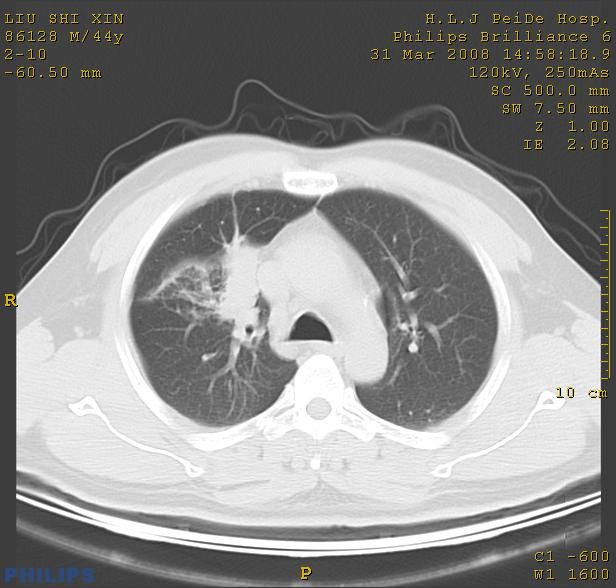

标题: CT13096:请分析胸膜下结节的影像基础是什么 有病理结果 [打印本页]

标题: CT13096:请分析胸膜下结节的影像基础是什么 有病理结果

中心型肺癌并阻塞性肺炎、两肺及胸膜多发转移。

结节灶与血管末梢相通象转移灶;小三角状尖部有纤维索是胸膜拉扯征;纵隔旁大片实性影有点状钙化;周围有名显纤维瘢痕征可考虑瘢痕癌

支持 右肺上叶前段肺癌并阻塞性肺炎、两肺及胸膜多发转移。

胸膜下结节是转移了。

本病例有病理结果是,鳞状上皮癌,胸膜下结节影病现诊断的肿大淋巴结,谢谢大家分析,请问胸膜下结节是肿大淋巴结怎么解释